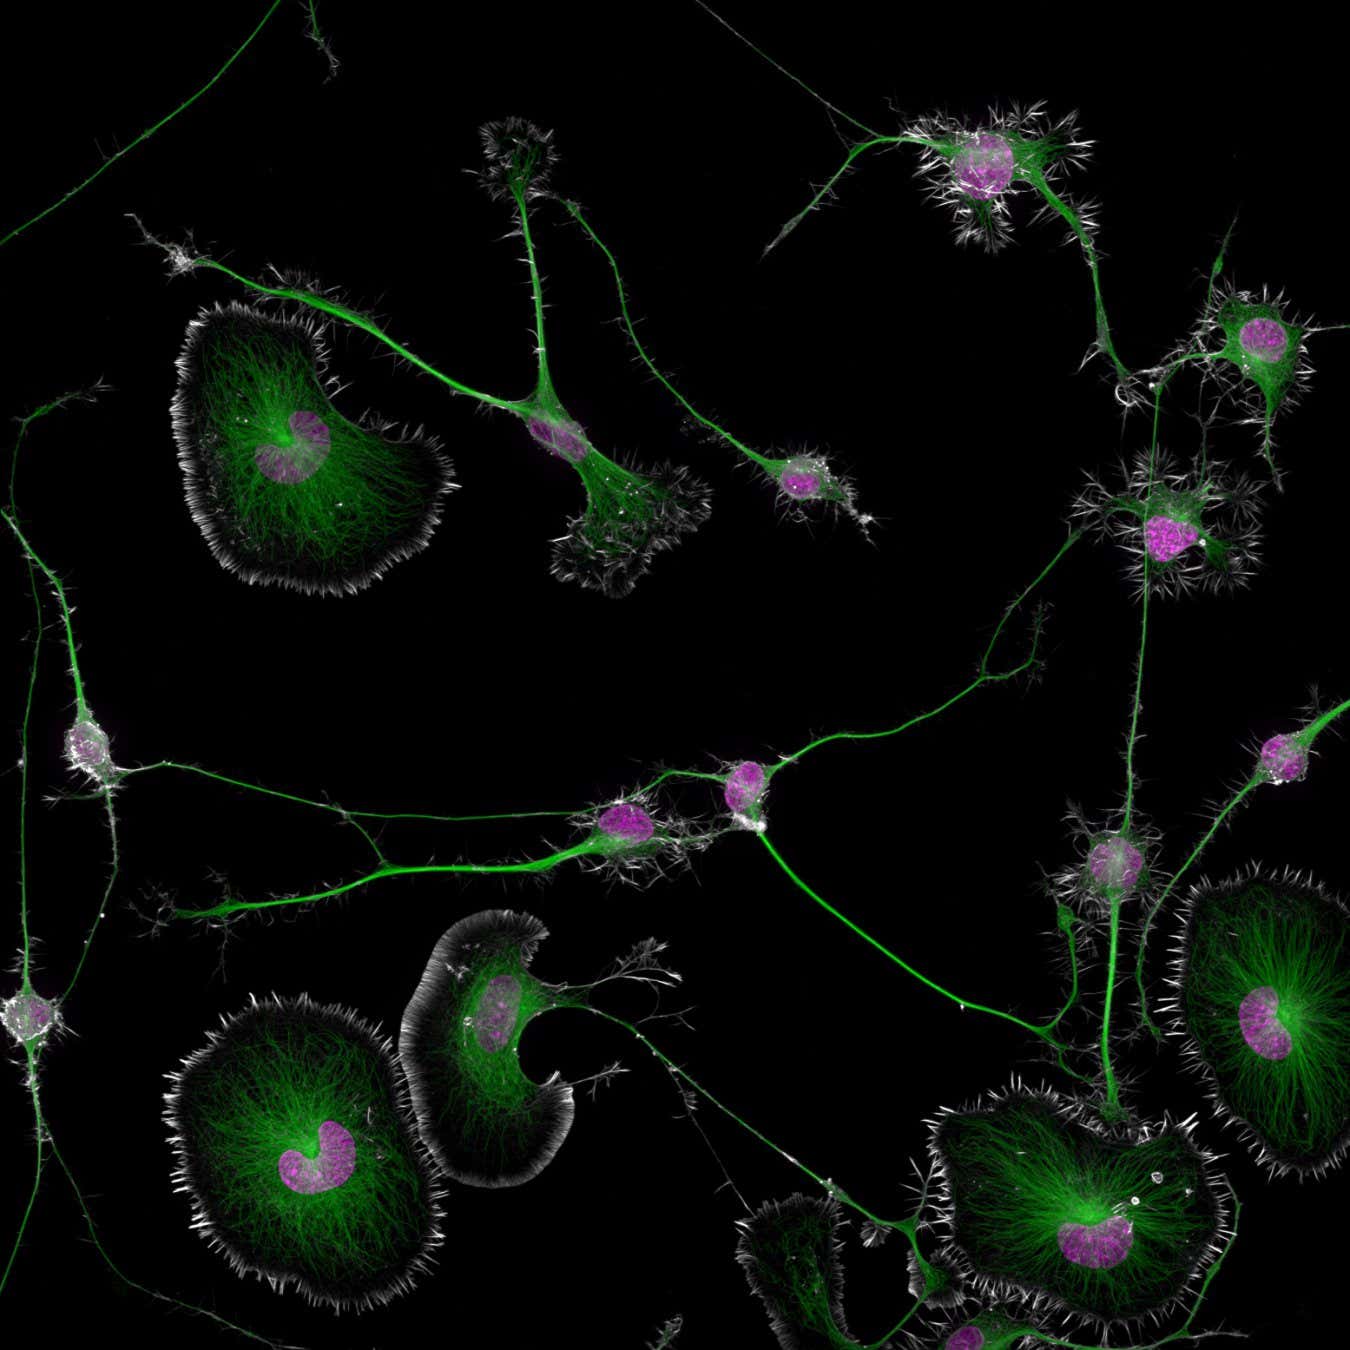

Células tumorales en el cerebro de un ratón

Bruno Cisterna/Nikon Pequeño Mundo

Una instantánea de una delicada red de células tumorales dentro del cerebro de un ratón se ha llevado el primer premio del Nikon Small World de este año. fotografía concurso, que celebra la microscopía.

Hebras verticales y muy compactas de una proteína conocida como actina bordean cada célula, que contiene revoltijos verdes de pequeños tubos, llamados microtúbulos, que rodean un núcleo violeta.

Bruno Cisterna Irrazábal de la Universidad de Augusta en Georgia, que tomó la foto, está explorando si la ruptura de las estructuras alrededor de los núcleos podría influir en el desarrollo de enfermedades neurodegenerativas, como la enfermedad de Alzheimer.

“Uno de los principales problemas de las enfermedades neurodegenerativas es que no entendemos completamente qué las causa”, dijo en un comunicado. “Para desarrollar tratamientos eficaces, primero debemos descubrir los conceptos básicos”.